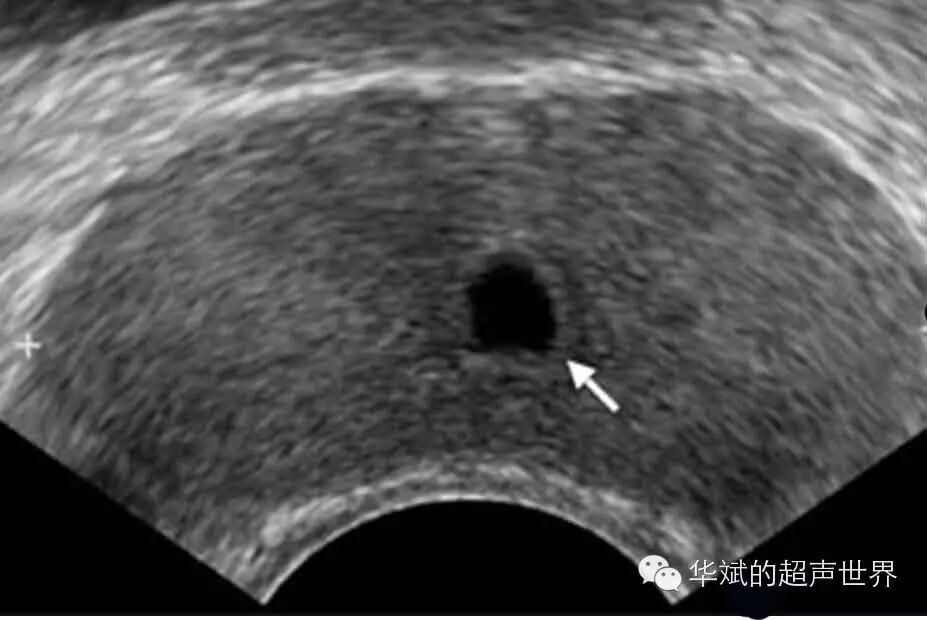

图5 前列腺小囊囊肿。位于中线上,前列腺偏后区域。